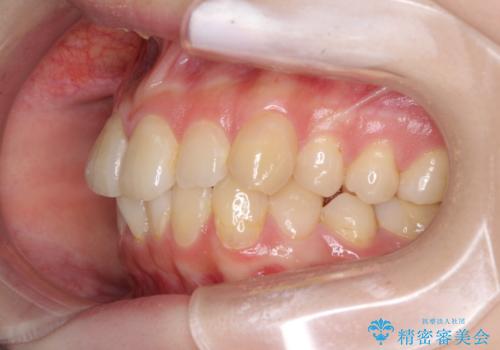

デコボコ歯列をきれいに インビザラインによる矯正治療

- 上下歯列全体のデコボコを気にして来院された患者様です。

主に下顎歯列全体の後方移動とIPR(歯と歯の間を削る)によってデコボコが解消するように設計し、インビザラインにより治療を行うこととしました。

奥歯の知覚過敏が顕著となり、その影響で奥歯の咬み合わせ改善のための顎間ゴムの装着ができず、咬合を仕上げるまでに長い期間を要することとなりました。